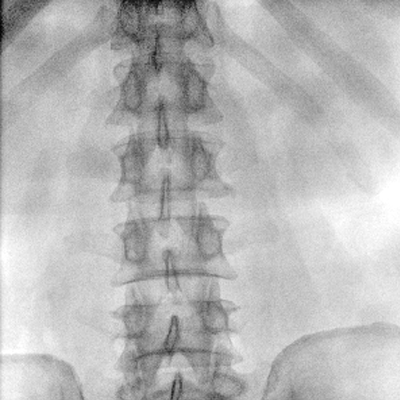

大尺寸動態(tài)平板探測器,高DQE、低噪聲、圖像清晰。采用多分辨率圖像增強處理技術(shù),不同部位不同圖像處理算法,滿足客戶多樣化的需求。

采用智能變頻脈沖透視技術(shù),優(yōu)化圖像質(zhì)量的同時降低輻射劑量,呵護醫(yī)患健康